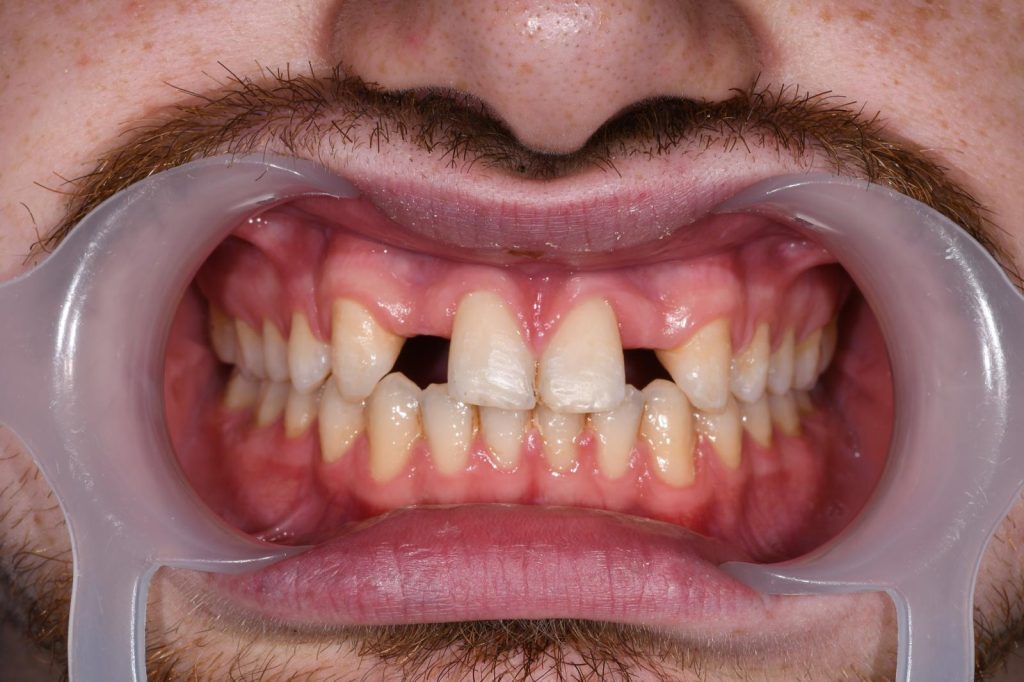

Mladi pacijent nam se obratio s problemom hipodoncije gornjih bočnih sjekutića. Nedostatak ovih zuba uzrokovao je razmak među prednjim zubima i nesklad u osmijehu.

Hipodoncija - nedostatak sjekutića

Prije ortodontske terapije